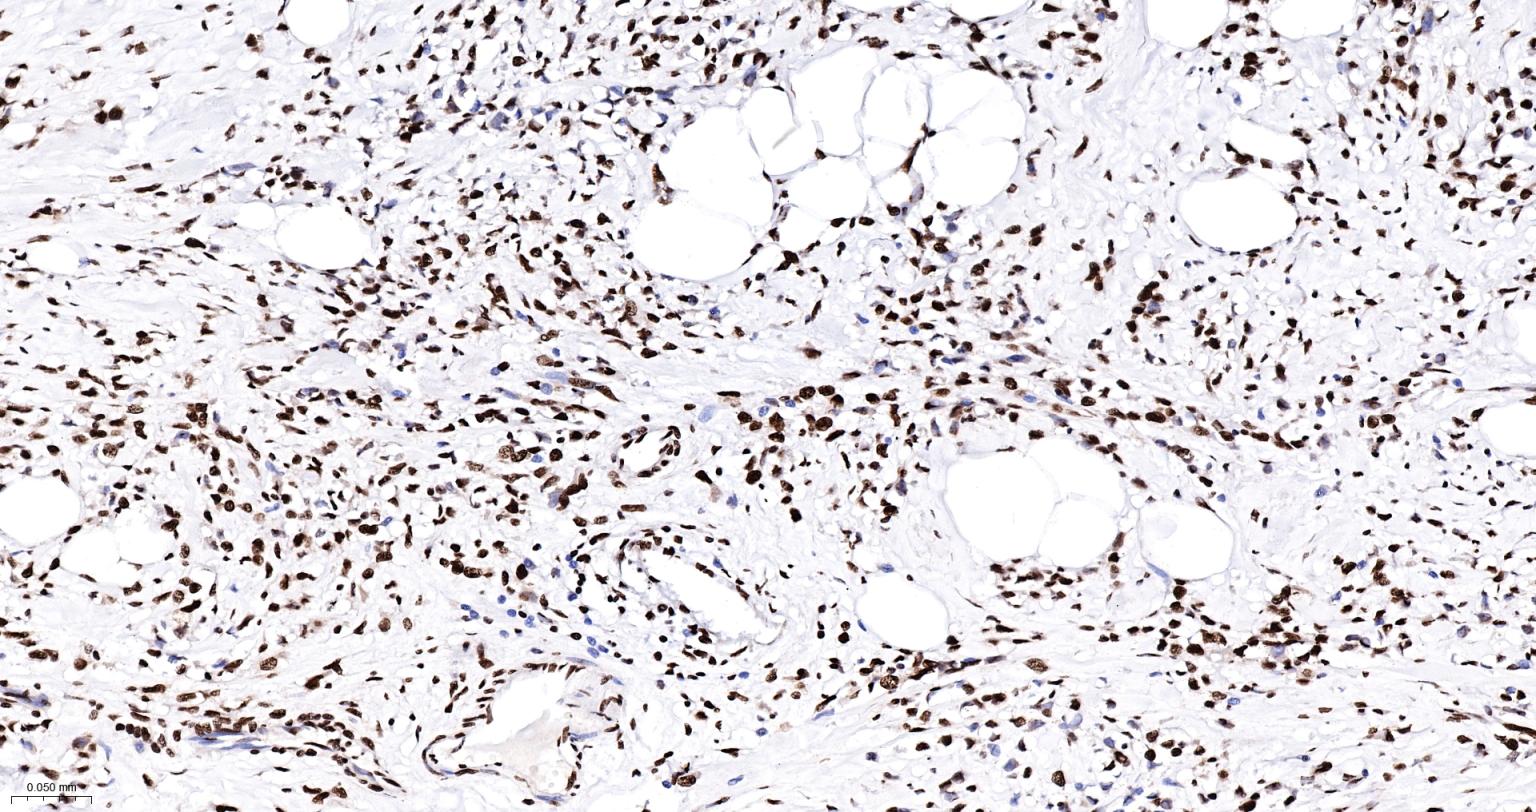

Paraformaldehyde-fixed, paraffin embedded Human Lung Cancer; Antigen retrieval by boiling in sodium citrate buffer (pH6.0) for 15 min; The section was incubated with hnRNP K Monoclonal Antibody, Unconjugated (bsm-61246R) at 1:200 overnight at 4°C, followed by conjugation to the bs-0295G-HRP and DAB (C-0010) staining.